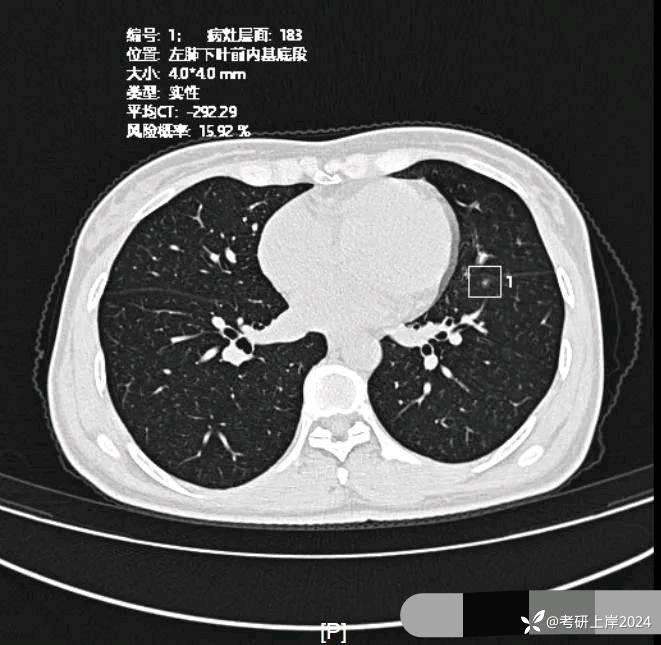

患者最近的检查有AI辅助诊断意见,找出的病灶分别如下:

病灶13:左下叶微小磨玻璃结节,边缘欠清,病灶过小,考虑少许纤维增生或肺泡上皮增生可能性较大;

病灶18:左下叶极淡密度结节,但轮廓却清,考虑肺泡上皮增生可能性大;

与2024年3月份复查时的对比,几乎没有变化。我的回复:两肺多达20几处结节,除了最后一处实性的考虑良性的,其他的都是磨玻璃密度,整体轮廓较清的,这在3月份的AI诊断上都有截图,其中最主要的几处就是我另外再截图了发来的这几处。它们也仍算是磨玻璃密度,病理大概会是原位癌可能性大,个把最坏可能是微浸润性腺癌,其实说不上明显实性成分,只是右上叶的那三处,最靠纵隔的那枚有血管穿过,显得像是混合密度,但肿瘤的成分仍是磨玻璃的。鉴于多发,又无法都通过手术全部切除,我的想法仍是再观察随访为主,待主病灶进展到有风险了再来考虑干预处理主病灶,并到时候兼顾同侧的其他结节是否顺带解决一部分。目前先随访,意见供参考!感悟:今天为什么要分享其实挺常见的这种多发磨玻璃病例?我想主要是由于结友问诊了这么多医生,仍在继续问,说明她虽然这些结节目前风险不大,但对她的心理造成了很大的压力,这也是结友最常见的心理状态。我觉得心理的崩溃或不断钻牛角尖的思考或许在短期内导致的害处更甚于结节本身!她问了这么多医生,肯定大部分都认为能随访,目前也没有风险大到定得赶紧处理的病灶,但她仍在不停的问诊,总想得到更让其踏实的答案。但哪位医生能说这些不是恶性范围的呢?谁能告诉她这是正常的呢?那不可能呀!已对查出多发结节,致病因素不明、预防措施没有、切又切不光、用药也不用!你说除了正确认识它、理性面对它,你能如何?在问诊中,总是有结友问到底有没有增长1毫米?CT值有没有增加?血管有没有进入?空泡有没有?实性成分有没有以及占多少?这些作为患者自己定要去纠结有何益?能说明什么问题呢?总体上,如果像今天这位结友医院提供AI辅助诊断意见,那是大小、体积、CT值、风险程度都会列的清清楚楚。但实际上在临床工作中,医生并不必这样按数值去判断风险或决定是否手术,如果这样还需要医生干嘛,AI全部会给出意见,AI说该开刀的转给胸外科、AI说可随访的回家下次来复查、AI说有风险的去消融等等。事实上我一直认为,我们看肺多发结节,关键就抓住:1、最主要的病灶风险如何:如果主病灶仍是危险性不高能随访,那么既无必要去数一共是10处还是15处,抑或20处,都没有意义,因为反正是按时复查就行;2、不同时期影像的对比,过于细微的差别,当其不足以改变临床决策的时候,就失去了深究的意义:纯磨只需随访的,你是5毫米也好,7毫米也罢,有何相干?反正仍不需干预处理。实性结节怕它危险,但若2毫米、3毫米,连影像特征都看不明白,更不可能为了这类结节去切下来化验,那么总在担心到底良性还是恶性,会不会是小细胞癌有何用?所以我在临床工作中,基本上不在意具体大小,也不去测CT值,关注一是实性成分有没有;二是血管有没有进入以及异常增粗;三是对比最早的与最近的有没有明显变化。放平心态、理性面对,该随访时按时随访,该干预时下决心干预!